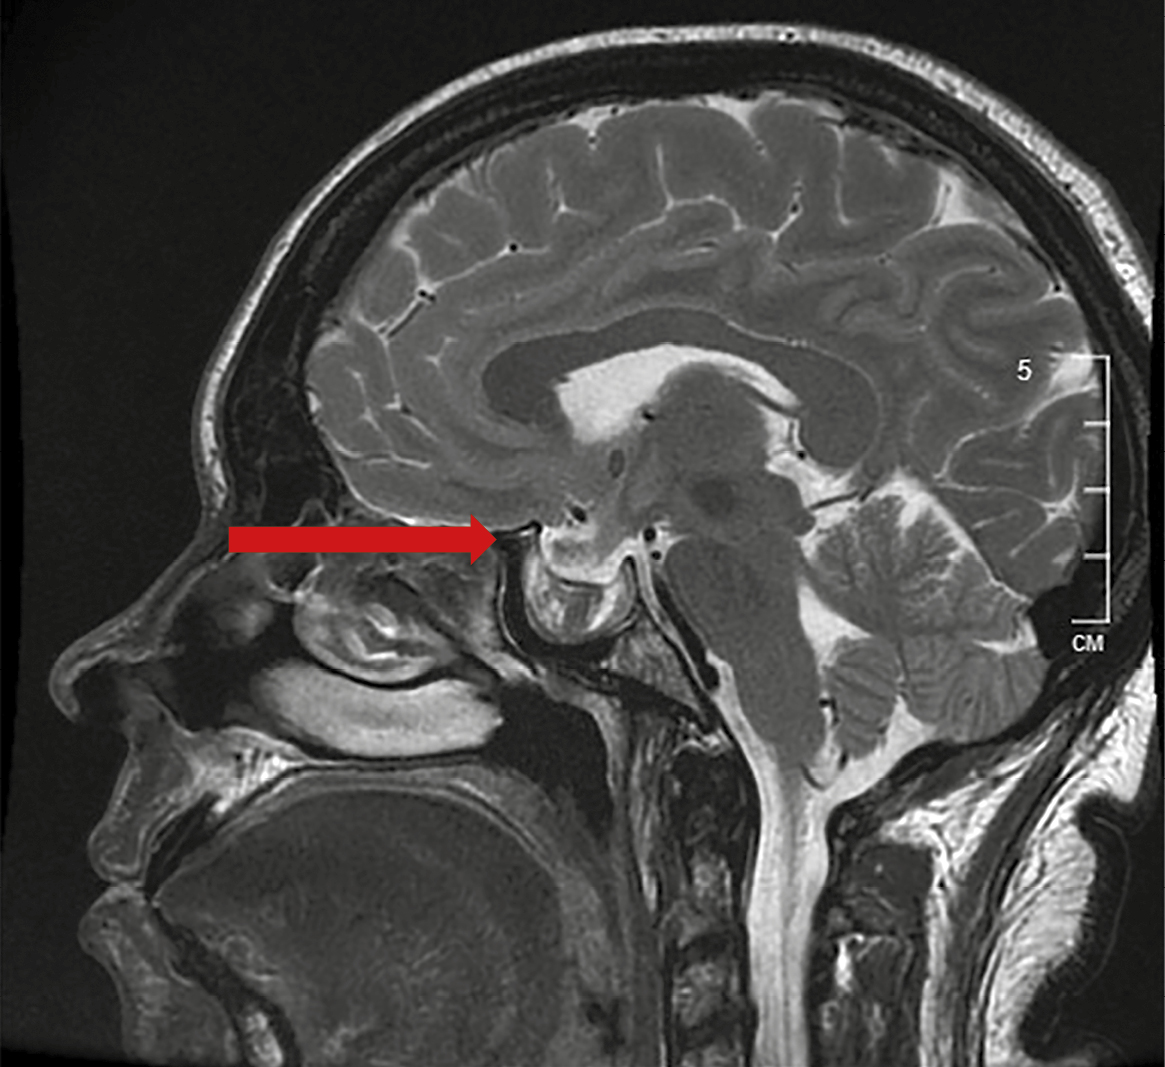

1. Figure 1. MRI of the brain with contrast enhancement from 11/23/2023. MR signs of previous apoplexy in the pituitary adenoma. | |